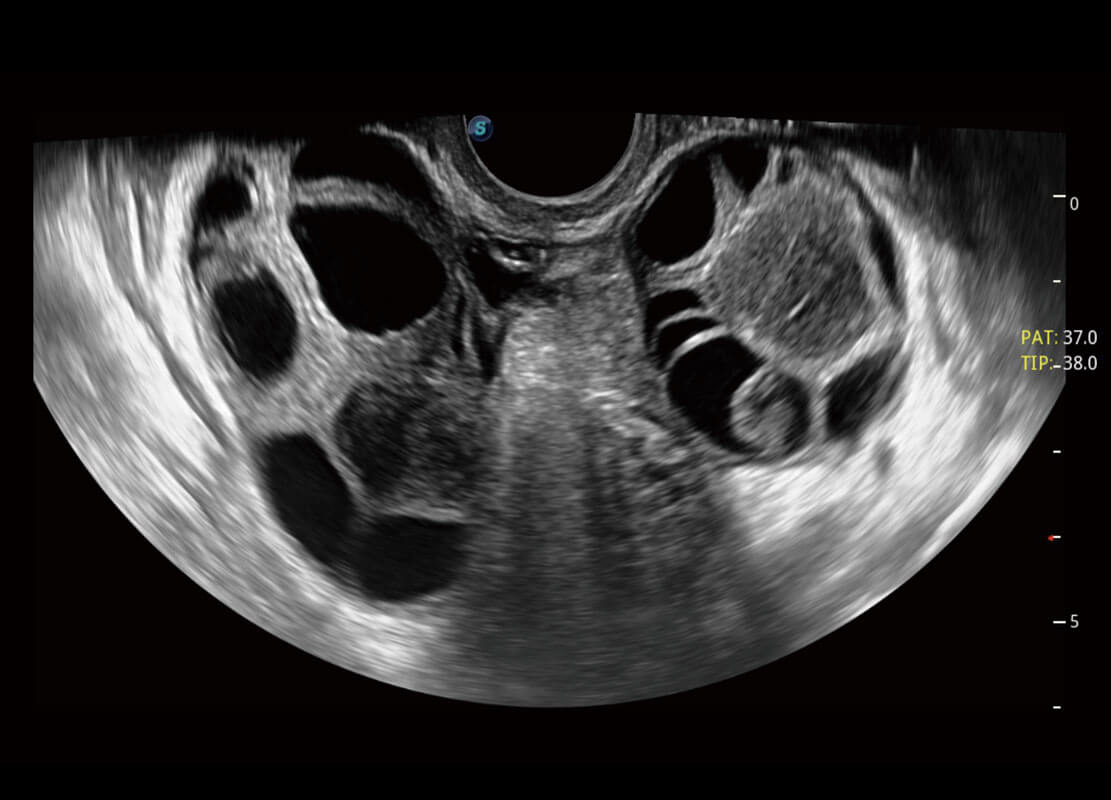

P60优异的图像质量搭载专科探头,在妇科基础疾病的诊断、卵泡生长的监测、输卵管通畅情况的判别等方面为您提供生殖应用方案。

腔内妇科-卵巢

腔内三维-宫内节育器

腔内三维-光影成像